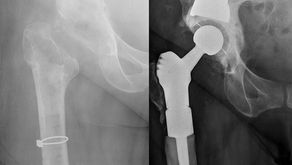

QUALITY OF LIFE AFTER HIP REPLACEMENT

Hip op patients assured surgery is ‘life-changing . ’ With more and more people in their fifties – and younger – facing a hip...